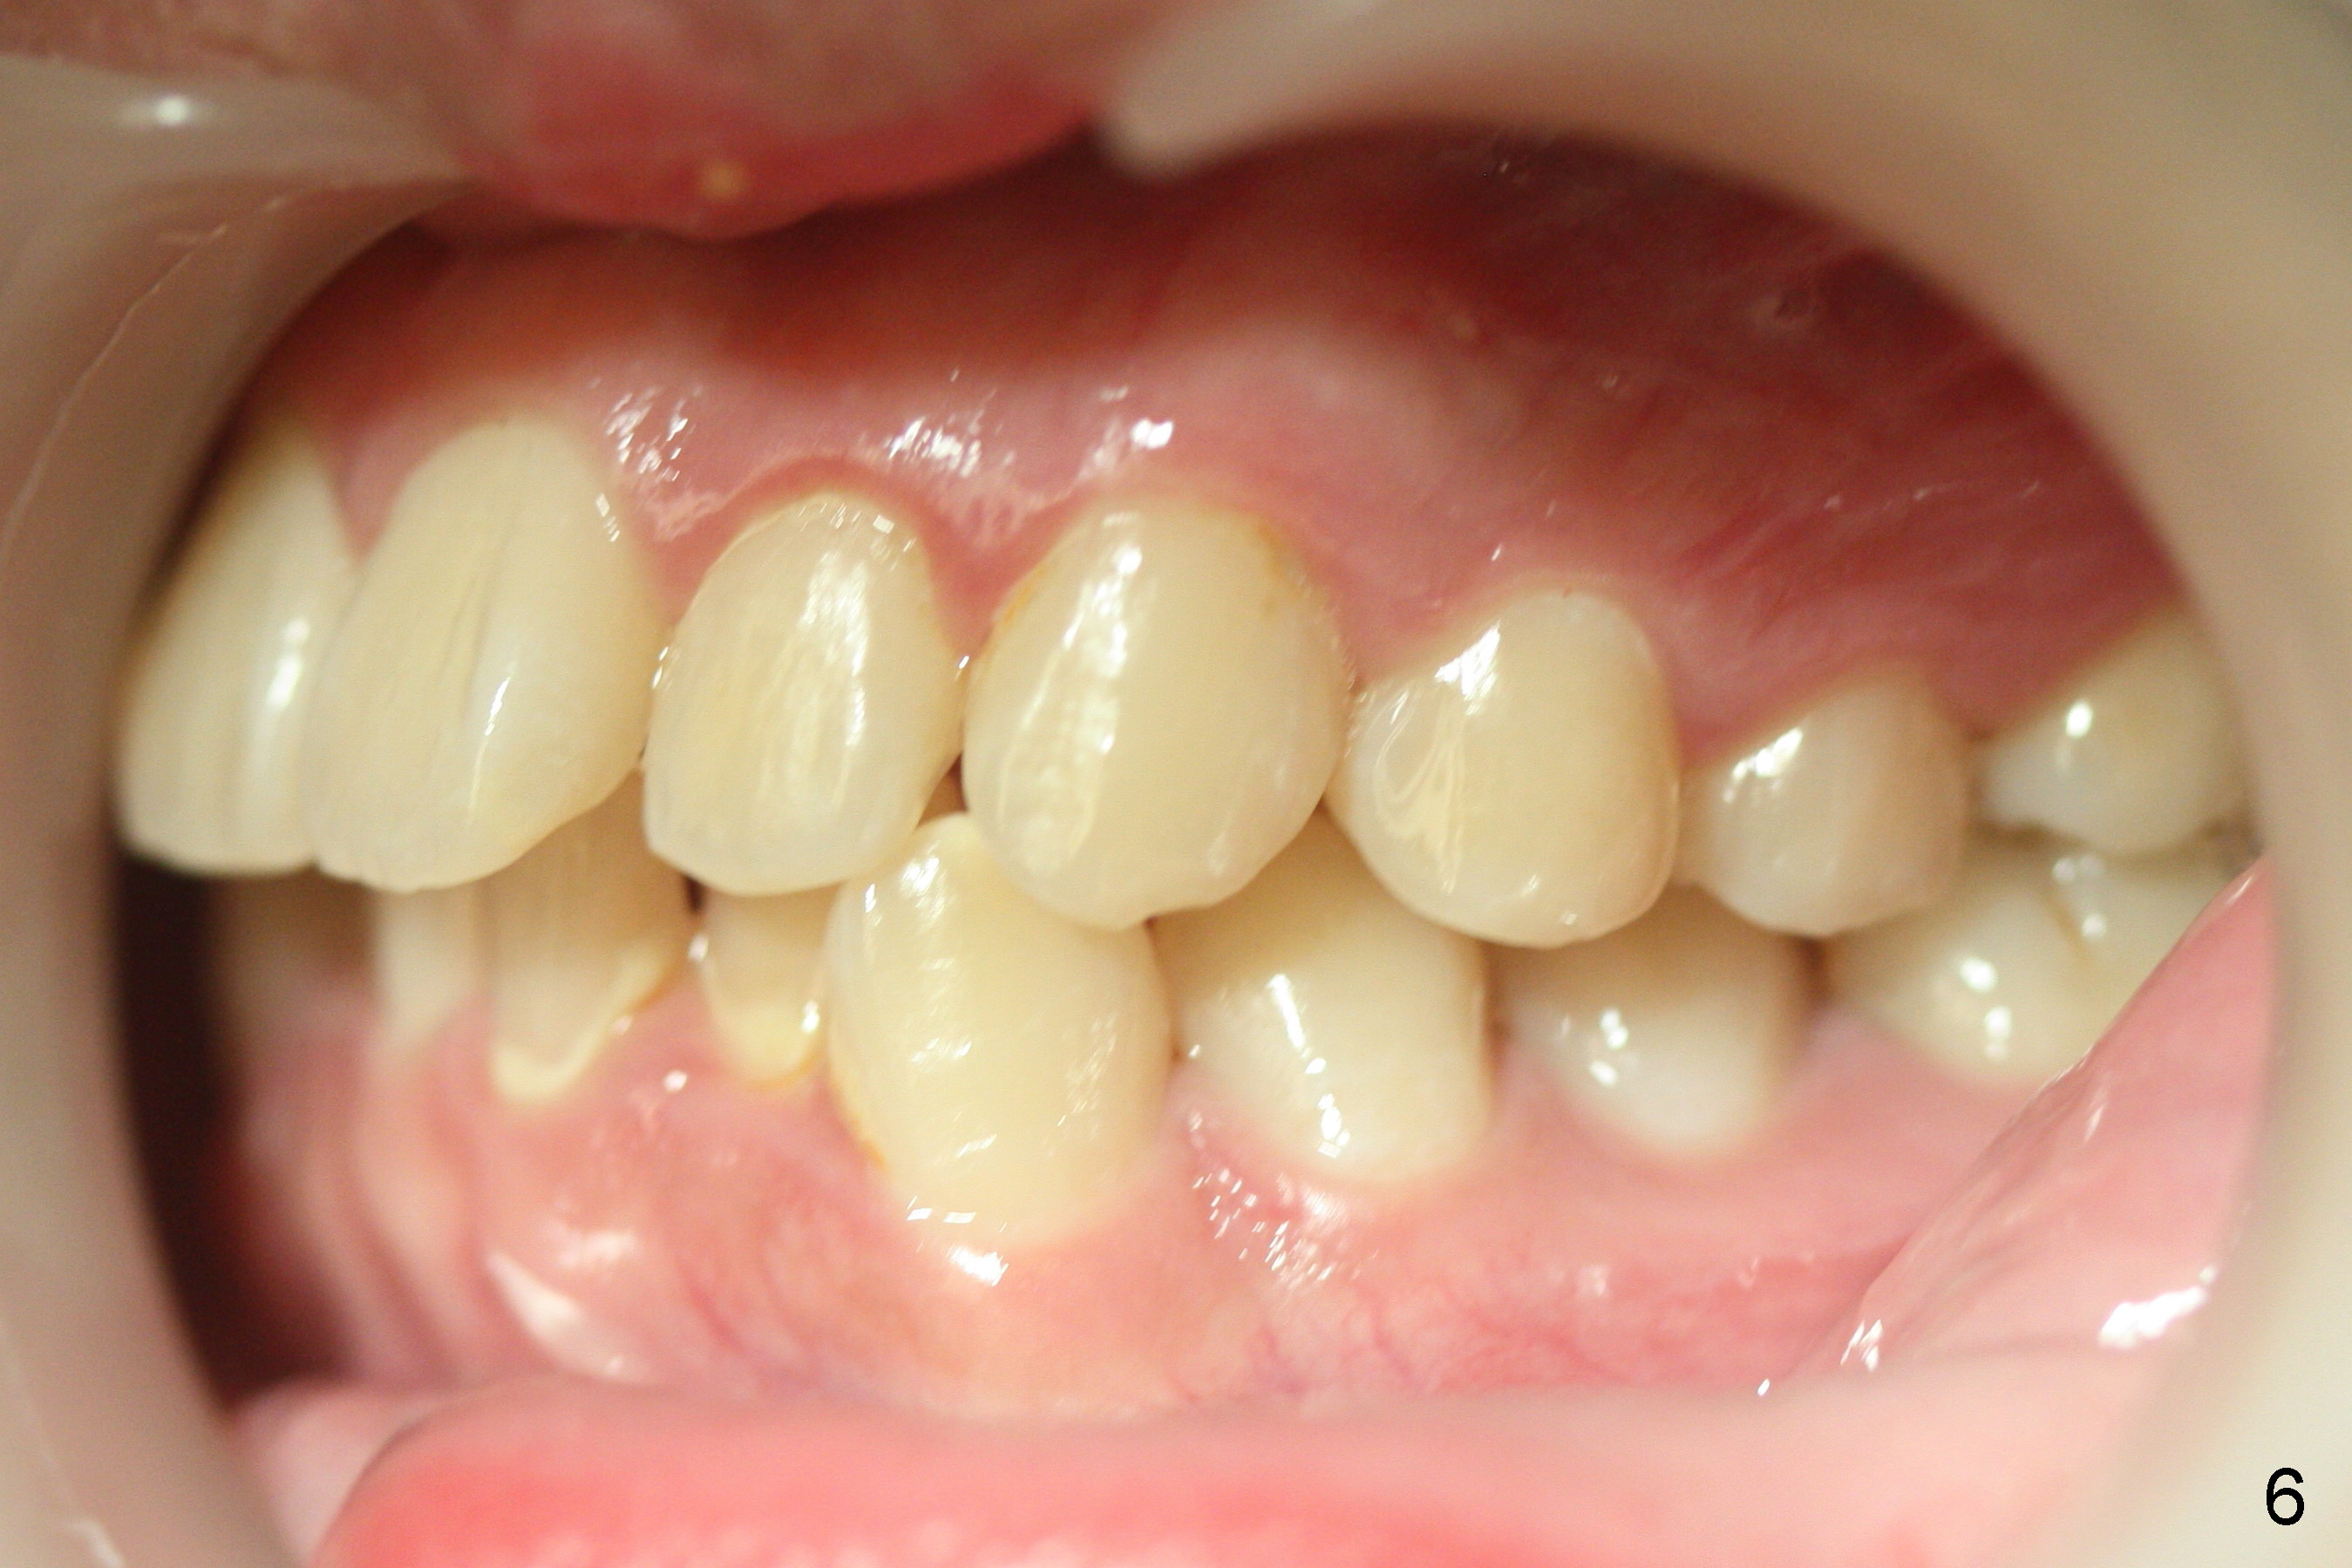

A 15-year-old man wants to improve the facial appearance.

Xin Wei, DDS, PhD, MS 1st edition 02/27/2017, last revision 09/09/2018